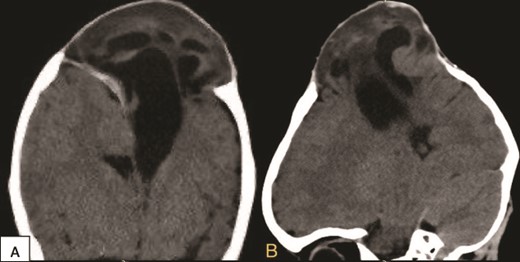

At the age of one month, the patient was diagnosed with sagittal craniosynostosis (Fig. 1), and by the age of 4 months, he underwent a strip craniectomy in another hospital to treat it without any acute complications; however, 2 weeks later his family noticed a bulging.

Initial computed tomography scan (CT) scan obtained when the patient was 3 months old showing sagittal craniosynostosis. (A) Superior axial view and (B) posterior view.